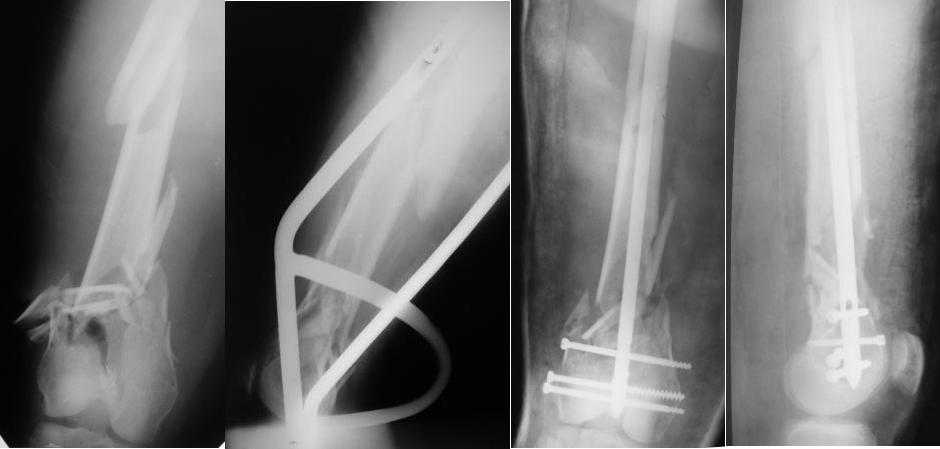

Re: Многооскольчатый перелом бедра

Приносим извенения за недостаток информации. Выкладываю все снимки. Стержень фирмы НПО ДЕОСТ(г.Пущино-на-оке)

-1. стержень в суставе,

Это не критично, в межмышелковой борозде,не на опроной поверхности, выступает из субхондральной кости, не факт что из хряща.Про надколенник Александр Николаевич уже писал.

-2. неправильная длинна винтов,

и толщина тоже. При такой длине хочется помощнее.

-3. ось конечности неправильная,

Вполне прилично. Если в боковой проекции рекувации нет. Где кстати боковая, хочется спросить у постмейкера.

2. Лучше борется с рекурвацией дистального отломка за счет угла Герцога.(В представленном примере "недопобороли")

В данном случае, на мой взгляд, если говорить о гвоздях, предпочтительней антеградное штифтование. Поскольку любая ретроградная конструкция не может иметь столь низкого расположения отверстий для винтов как антеградная из-за резьбового крепления.

Больная госпитализирована с тяжелой сочетанной травмой. Плюсом к перелому бедра имеется разрыв связок коленного сустава.